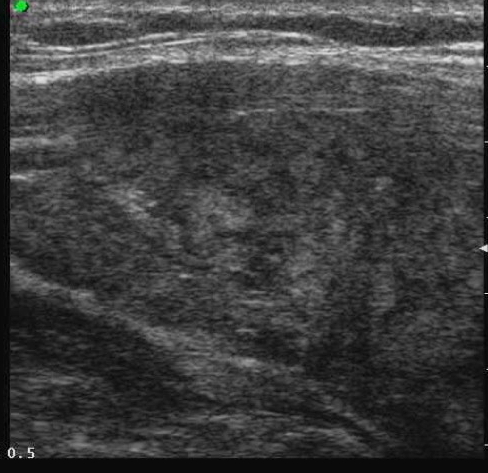

L’ipoecogenicità è dovuta all’aumento della quota cellulare rispetto alla colloide. Una marcata ipoecogenicità (simile a quella dei muscoli pre-tiroidei) è associata ad aumento del rischio di malignità con elevata specificità (fig. 10); talvolta può essere difficile distinguerla dall’ecogenicità di una raccolta liquida densa, ma l'uso del Doppler e i cambiamenti di posizione sono dirimenti nei casi dubbi. È importante differenziarla dalla debole ipoecogenicità (valutata rispetto al parenchima tiroideo circostante), perché questa è comune tanto alla patologia maligna che benigna e ha una minore accuratezza diagnostica (fig. 11).

Figura 11. Nodulo debolmente ipoecogeno: a sinistra scansione trasversale, a destra scansione longitudinale.